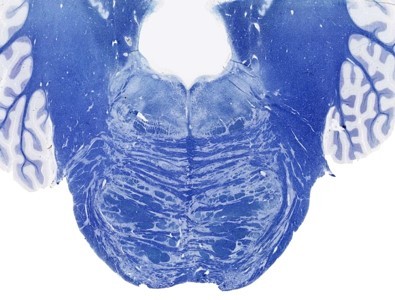

Upper pons

SLICE 3: Upper pons—main features- superior cerebellar peduncle, fourth ventricle, MLF, pontocerebellar fibers and top of middle cerebellar peduncle, medial lemniscus, spinothalamic tract, corticospinal fibers (disaggregated